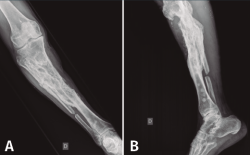

Se trata de un paciente varón de 52 años con antecedente de fractura de meseta tibial tratada mediante osteosíntesis y aporte de injerto de hidroxiapatita y posterior retirada del material de osteosíntesis tras la consolidación de la fractura. Al cabo de 6 años presenta fístula en la cara anterointerna del extremo proximal de la tibia.

Figura 5. Radiografías de frente y de perfil del extremo proximal de la tibia donde se objetiva la cavidad en la tibia con presencia de material granulado en su interior.

En el estudio radiológico (Figura 5) se objetiva imagen cavitaria en el extremo proximal de la tibia con presencia de material granulado del injerto realizado.

Figura 7. Radiografías de frente y de perfil del extremo proximal de la tibia tras el desbridamiento de la cavidad y el relleno con bolas de cemento con antibiótico.

Con el diagnóstico de osteítis crónica de la tibia se realiza desbridamiento óseo de la cavidad y amplia resección ósea de cortical tibial medial, y relleno de la cavidad con bolas de cemento con antibiótico (Figura 7), con posterior tratamiento antibiótico.

Figura 8. Radiografías del extremo proximal de la tibia donde se objetiva la correcta incorporación del injerto aportado.

Al cabo de 4 meses y tras la resolución del proceso séptico, se procede al relleno de la cavidad con injerto autólogo de cresta iliaca, cuya evolución fue hacia la incorporación de este (Figura 8).